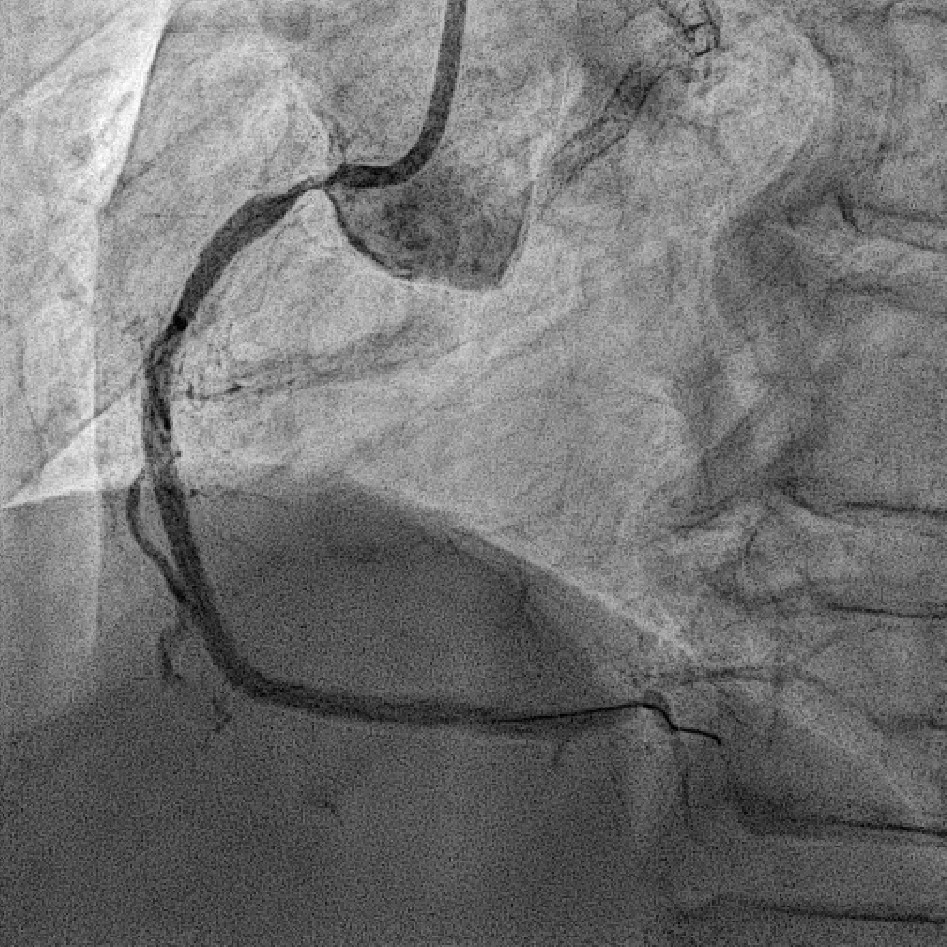

Coronary angiography revealed 81% in-stent restenosis at the right coronary artery ostium, worsened since February 2025. Proximal and mid RCA stents were patent; distal RCA was patent but smaller in caliber . Left main and LAD stents showed no progression, though 30–60% restenosis was seen in proximal to mid LAD. Left circumflex artery was nearly totally occluded from ostium to proximal segment, with preserved flow in mid and distal segments, similar to prior study.

We advanced a 6F JR 4.0 SH 100cm guiding catheter and crossed the RCA ostial lesion using a Fielder FC guidewire. Pre-dilatation was performed with Ryurei 1.5¡¿15mm balloon. IVUS was then performed, revealing a patent stent in the proximal to mid RCA. However, the ostial RCA stent was under-expanded, with smooth muscle compressing the stent from outside. Balloon pre-dilatation was carried out using an NC Euphora 4.0¡¿12mm balloon, inflated up to 22 bar. However, the lesion was resistant and could not be fully dilated. We then applied a 4.0mm intravascular lithotripsy balloon with a total of 100 shocks delivered. But the effect was still minimal. The IVUS showed limited additional plaque fracture or vessel expansion. We tried NC Sapphire II 4.5¡¿8 mm balloon inflation to 18 bar, but it was ineffective due to balloon slippage. The angiogram after oversized NC dilation showed residual stenosis of 59%. We then selected a Wolverine Cutting Balloon 4.0¡¿10 mm and initiated dilation to 6 bar, which resulted in easy slippage again. Subsequent oversized dilations were performed at 18 bar, after which the lesion was successfully dilated. Using a Runthrough Floppy guidewire with the floating wire technique, a drug-eluting stent Biofreedom Ultra 4.0¡¿14 mm was deployed in the ostial RCA ISR. We inflated at 14 bar for 14 seconds, repeated twice. Final post-dilatation was performed with an Accuforce 4.0¡¿15mm balloon. The final IVUS showed good stent placement and expansion. We closed the procedure.